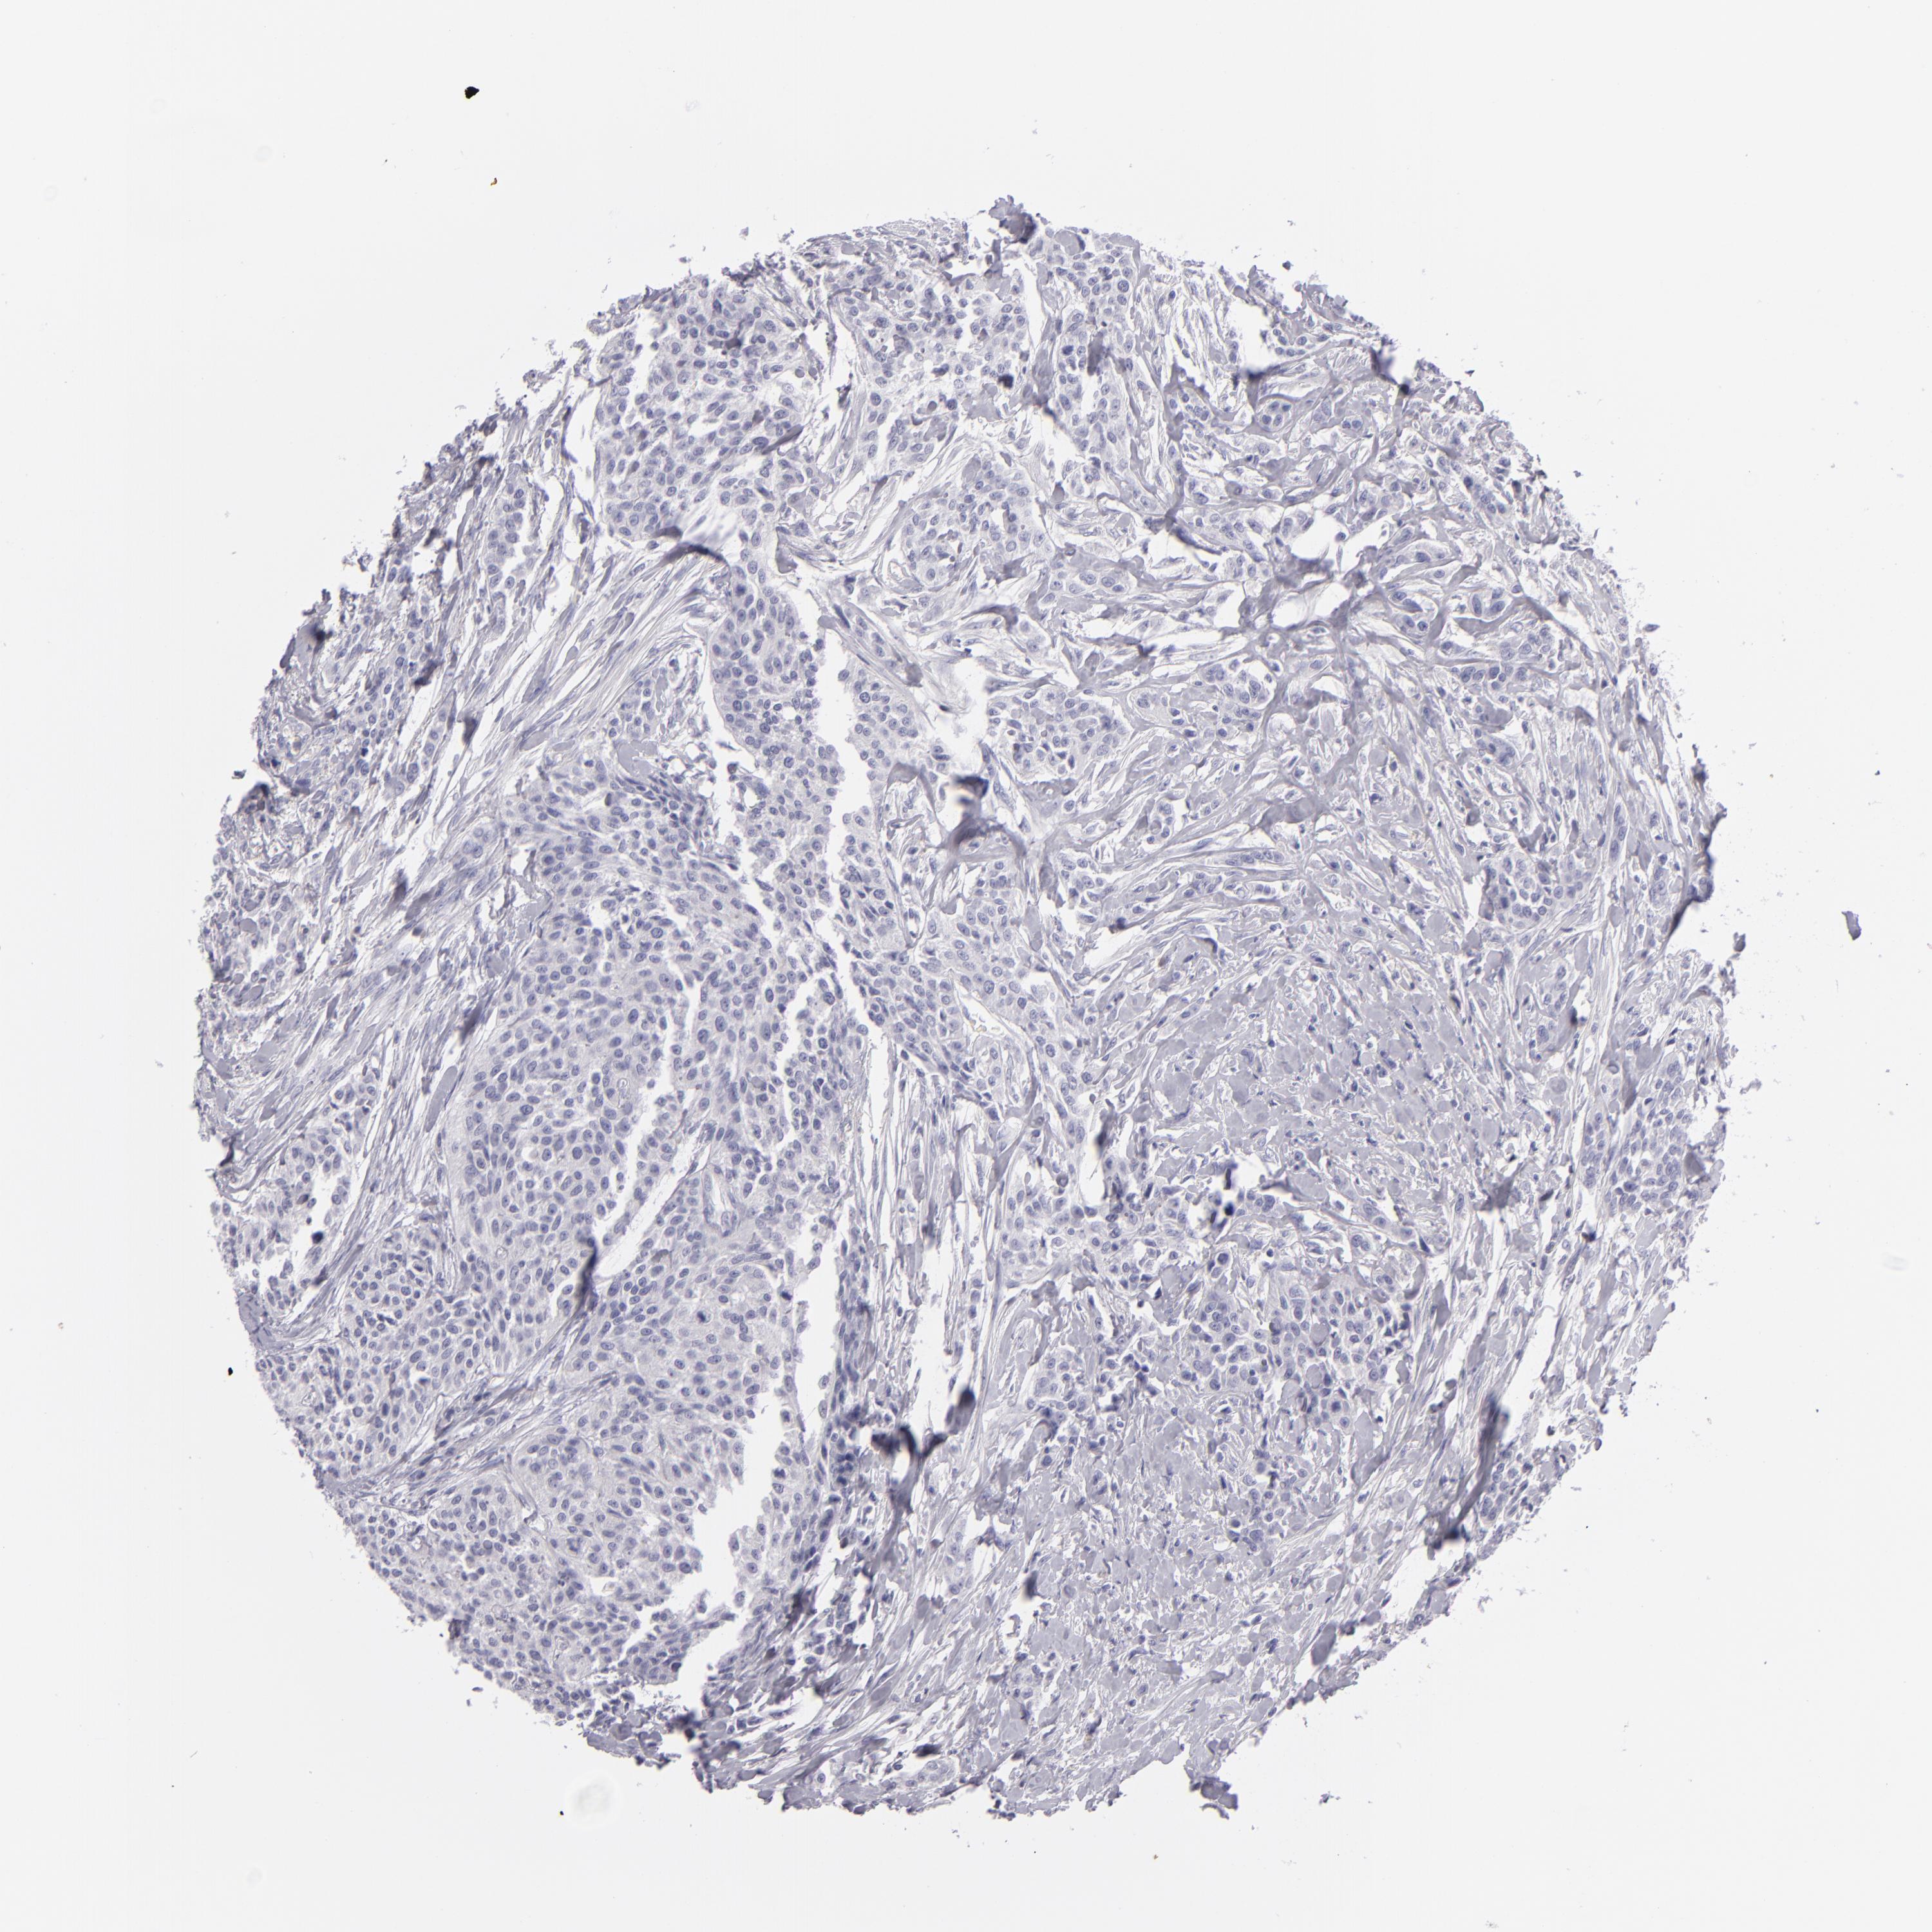

UROTHELIAL CANCER - Protein expressioni

A mouse-over function shows sample information and annotation data. Click on an image to view it in a full screen mode. Samples can be filtered based on level of antibody staining by selecting one or several of the following categories: high, medium, low and not detected. The assay and annotation is described here.

Antibody stainingi

Antibody staining in the annotated cell types in the current human tissue is reported as not detected, low, medium, or high, based on conventional immunohistochemistry profiling in selected tissues. This score is based on the combination of the staining intensity and fraction of stained cells.

Each image is clickable and will lead to virtual microscopy that enables deeper exploration of all samples and also displays staining intensity scores, fraction scores and subcellular localization as well as patient and tissue information for each sample.

Antibody HPA044848

Antibody HPA056897

Antibody CAB002450

Staining

High

Medium

Low

Not detected

Intensity

Strong

Moderate

Weak

Negative

Quantity

>75%

75%-25%

<25%

None

Location

Nuclear

Cytoplasmic/membranous

Cytoplasmic/membranous,nuclear

Urothelial carcinoma, High grade

Urothelial carcinoma, NOS

Urothelial carcinoma, Low grade

Adenocarcinoma, NOS